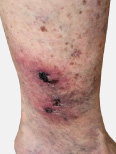

Continued increased pressure of blood in the leg veins causes changes to the skin that are typically noticed in the mid-calf to the ankle area. This condition, known as stasis dermatitis, is characterized by severe itching and redness of the skin followed by hyperpigmentation (discoloration of the skin due to deposition of iron pigments). This is followed by induration (thickening of the skin) and dermal fibrosis (scar tissue): a condition known as Lipodermatosclerosis. There may be atrophie blanche (smooth, ivory-white plaques surrounded by hyperpigmentation). The final stages of chronic venous insufficiency are related to the breakdown of skin and the formation of poorly healing leg ulcers (sores). There is a higher risk of local skin infection (cellulitis), sepsis (blood poisoning), and osteomyelitis (infection of the bone).

Dona is an "active" female who came to us in a wheelchair. She has lived with ulcers in both of her legs for several years. She has received wound care for numerous years without long-term relief; ulcers and skin infections became recurrent problems for her. She has also lived with substantial leg swelling, leg cramps and extreme sensitivity to touch. She has restless leg syndrome and was prescribed medications, such as Requip. Still, the discomfort in her legs (at night) remained.

She received endovenous laser ablation of the "leaky" (refluxing) axial veins in both legs at Alsara Vein Clinic in Spring 2018. By the start of Summer 2018, the ulcers in her legs had completely healed. The swelling is almost nonexistent and, for the first time in several years, she can enjoy pain-free legs both during the day and at night.